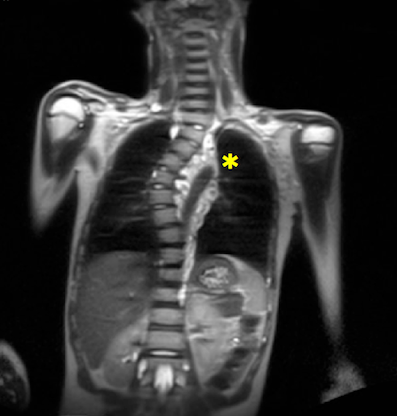

Dopo alcuni mesi veniamo contattati dalla curante del bambino, preoccupata per il rapido peggioramento della scoliosi, e decidiamo di sottoporre il piccolo a una RM rachide-encefalo che riscontra un’importante formazione solida in corrispondenza della curva scoliotica, estesa per circa 14 cm, compatibile con un neurofibroma plessiforme che, improntando i corpi vertebrali contigui, si porta ad avvolgere a manicotto l’aorta toracica discendente (Figura 2).